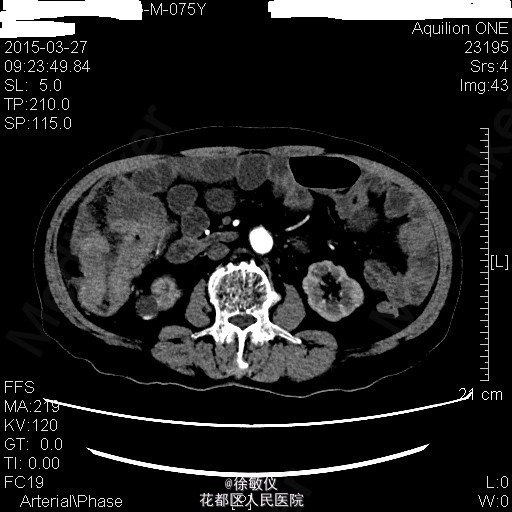

查体:生命体征平稳,贫血面容。腹软,全腹无压痛、反跳痛,右中腹可触及一大小约4*5cm包块,边界清晰,质稍硬。肝脾肋下未触及。 辅查:HGB 82g/L;CA19-9 625.97U/ml;CA-125 24.9U/ml;大便常规示:粪血红蛋白试验阳性。 全腹CT平扫+增强示:1、结肠肝曲及升结肠癌,浸润肠壁全层,周围多发淋巴结转移;2、直肠多发小息肉;直肠下段静脉曲张。